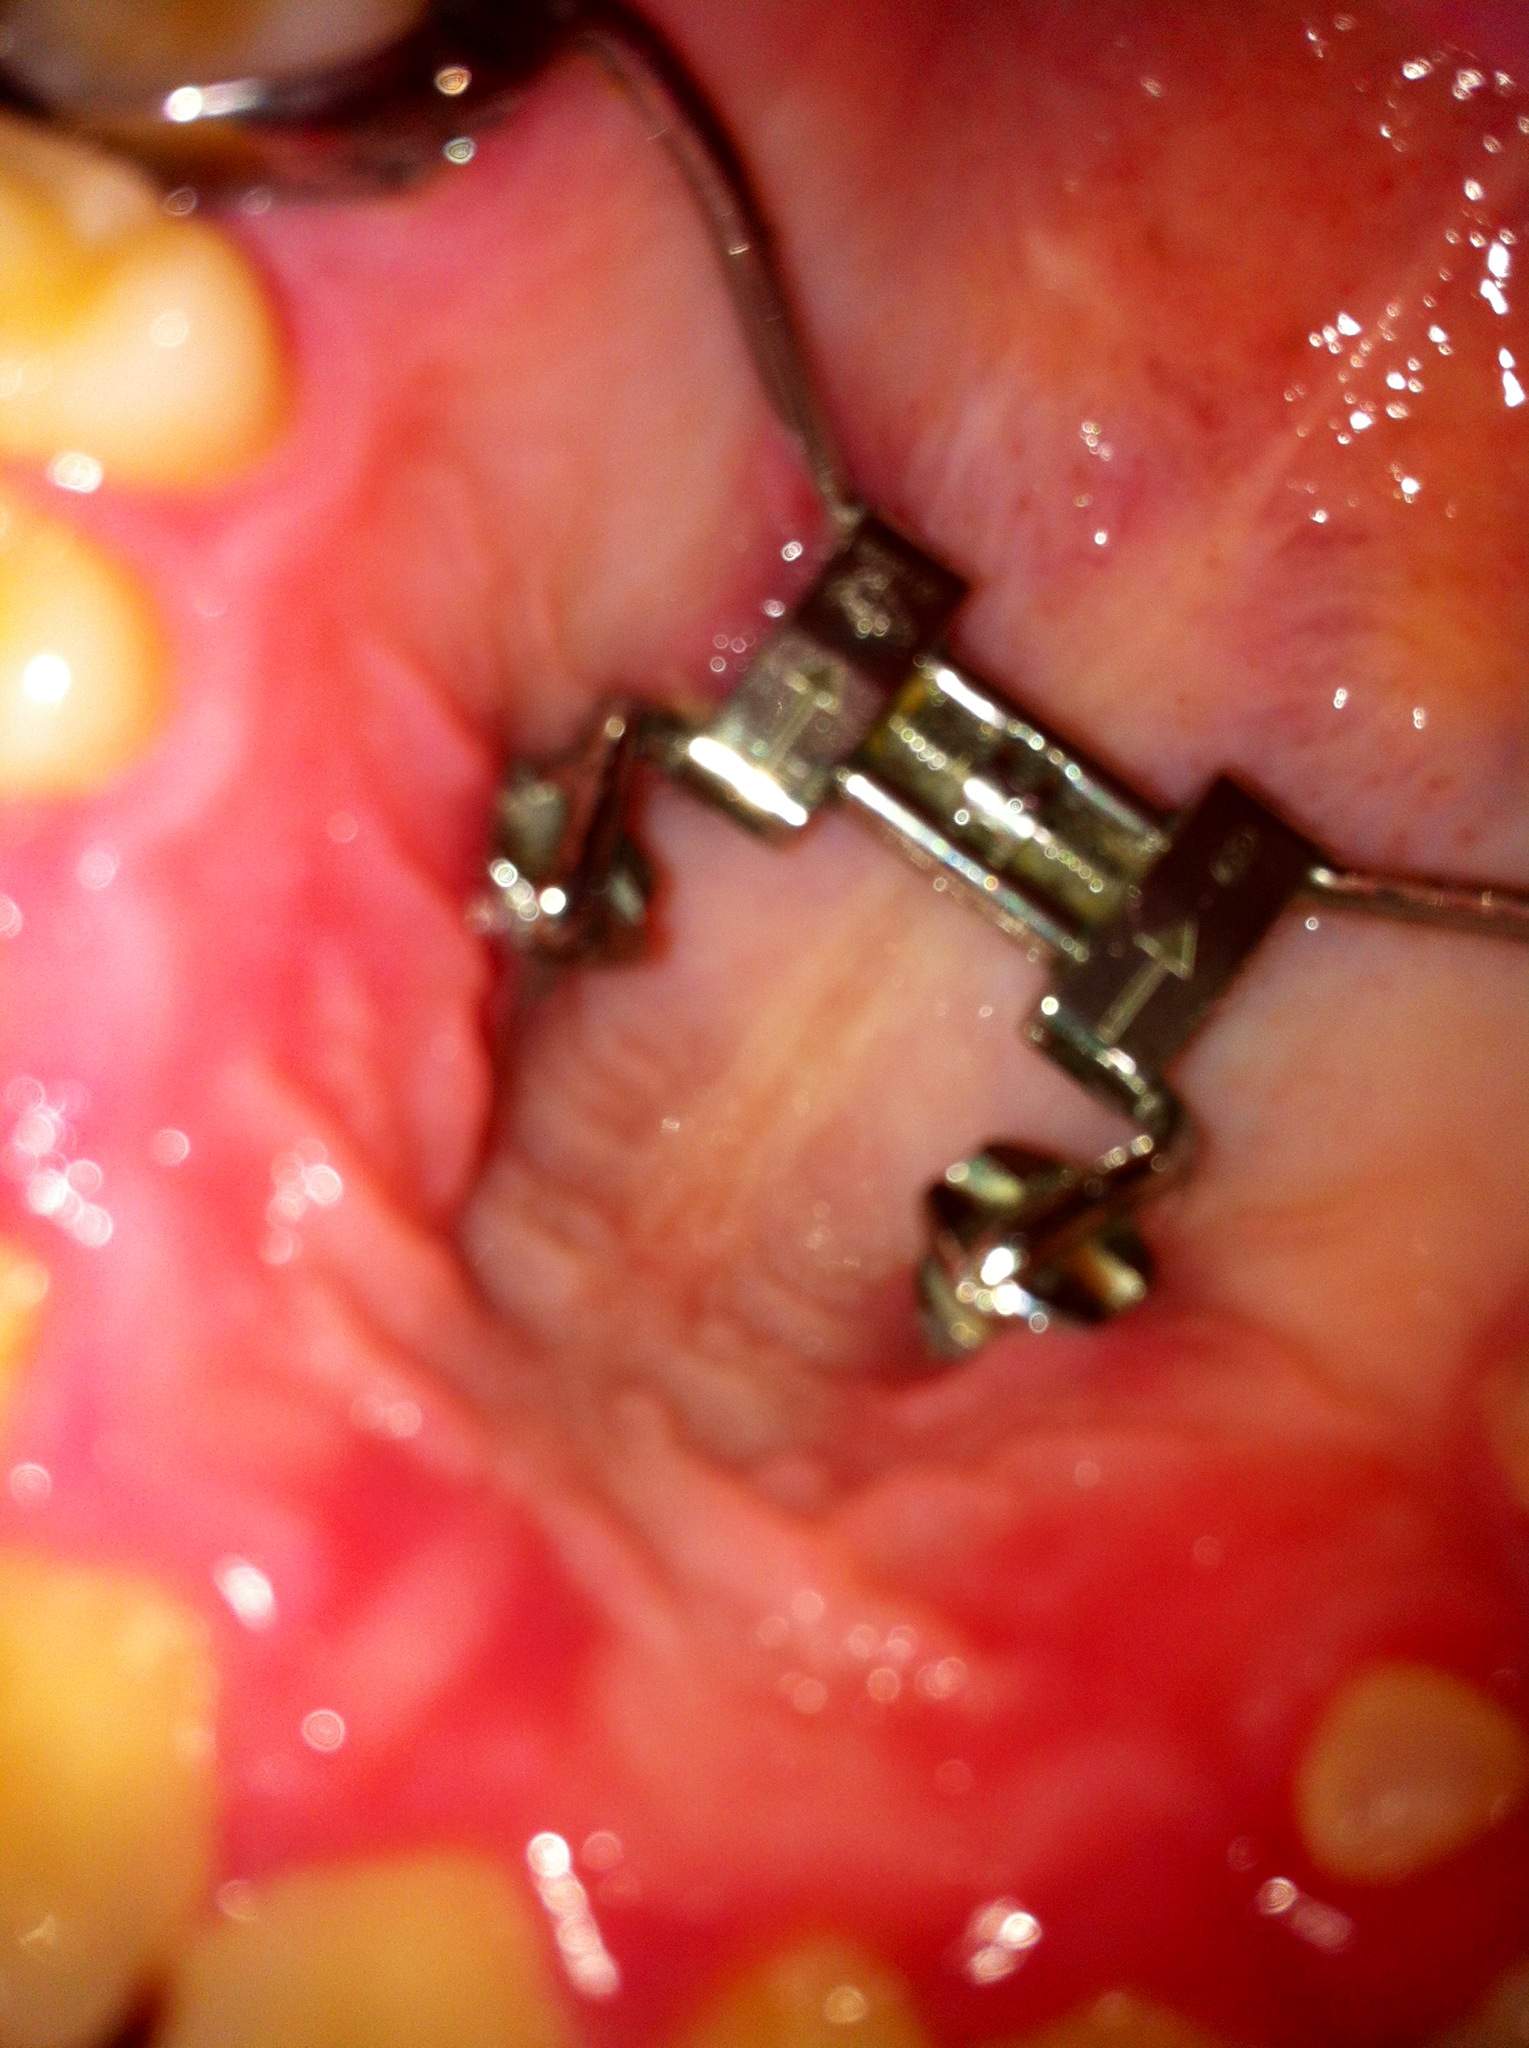

Erfahrungen Mit Gaumenbügel Und Headgear? (Zahnspange, Kfo)

Erfahrungen mit Gaumenbügel und Headgear? (Zahnspange, Kfo) www.gutefrage.netKinoposter Zu »Guardians Of The Galaxy« (2014) – SF-Fan.de